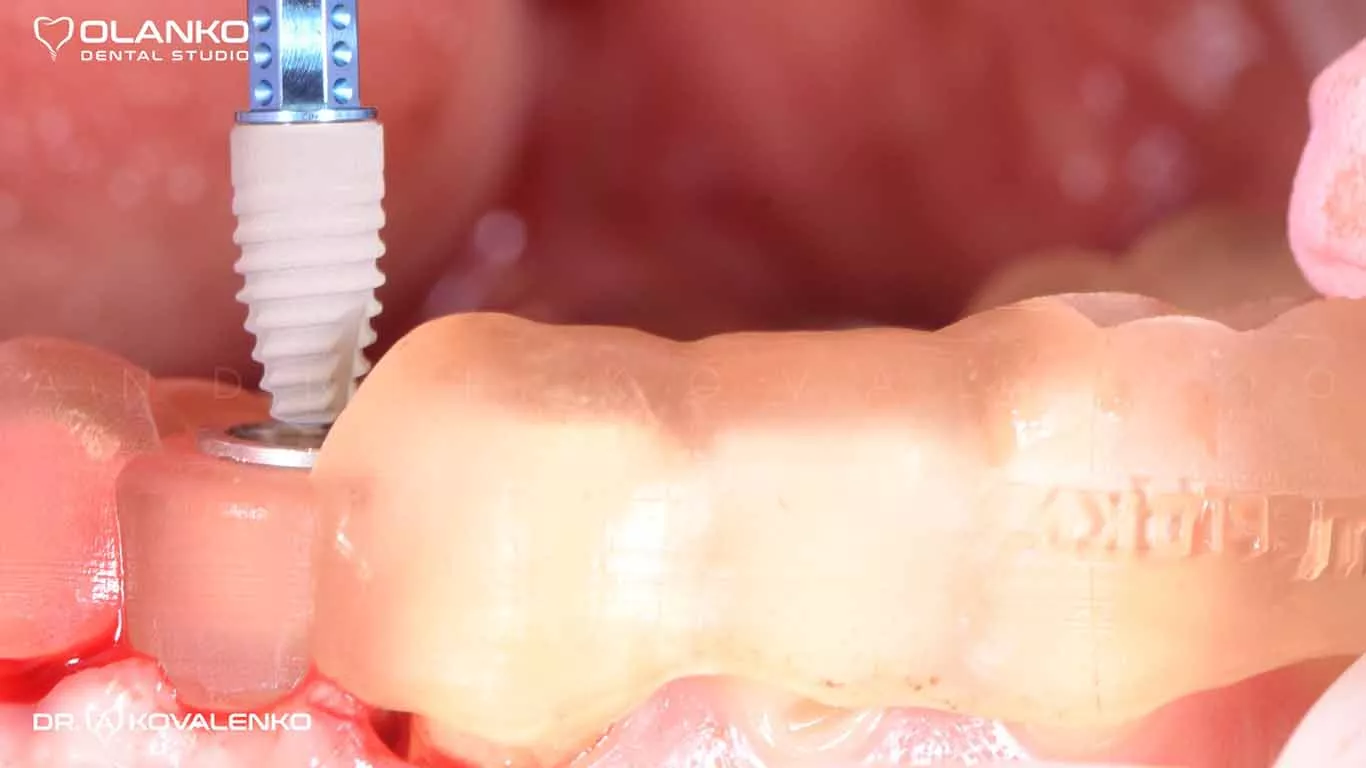

Фото імпланта Straumann під час установки за допомогою  шаблона:

Фото імпланта Straumann під час установки за допомогою  шаблона